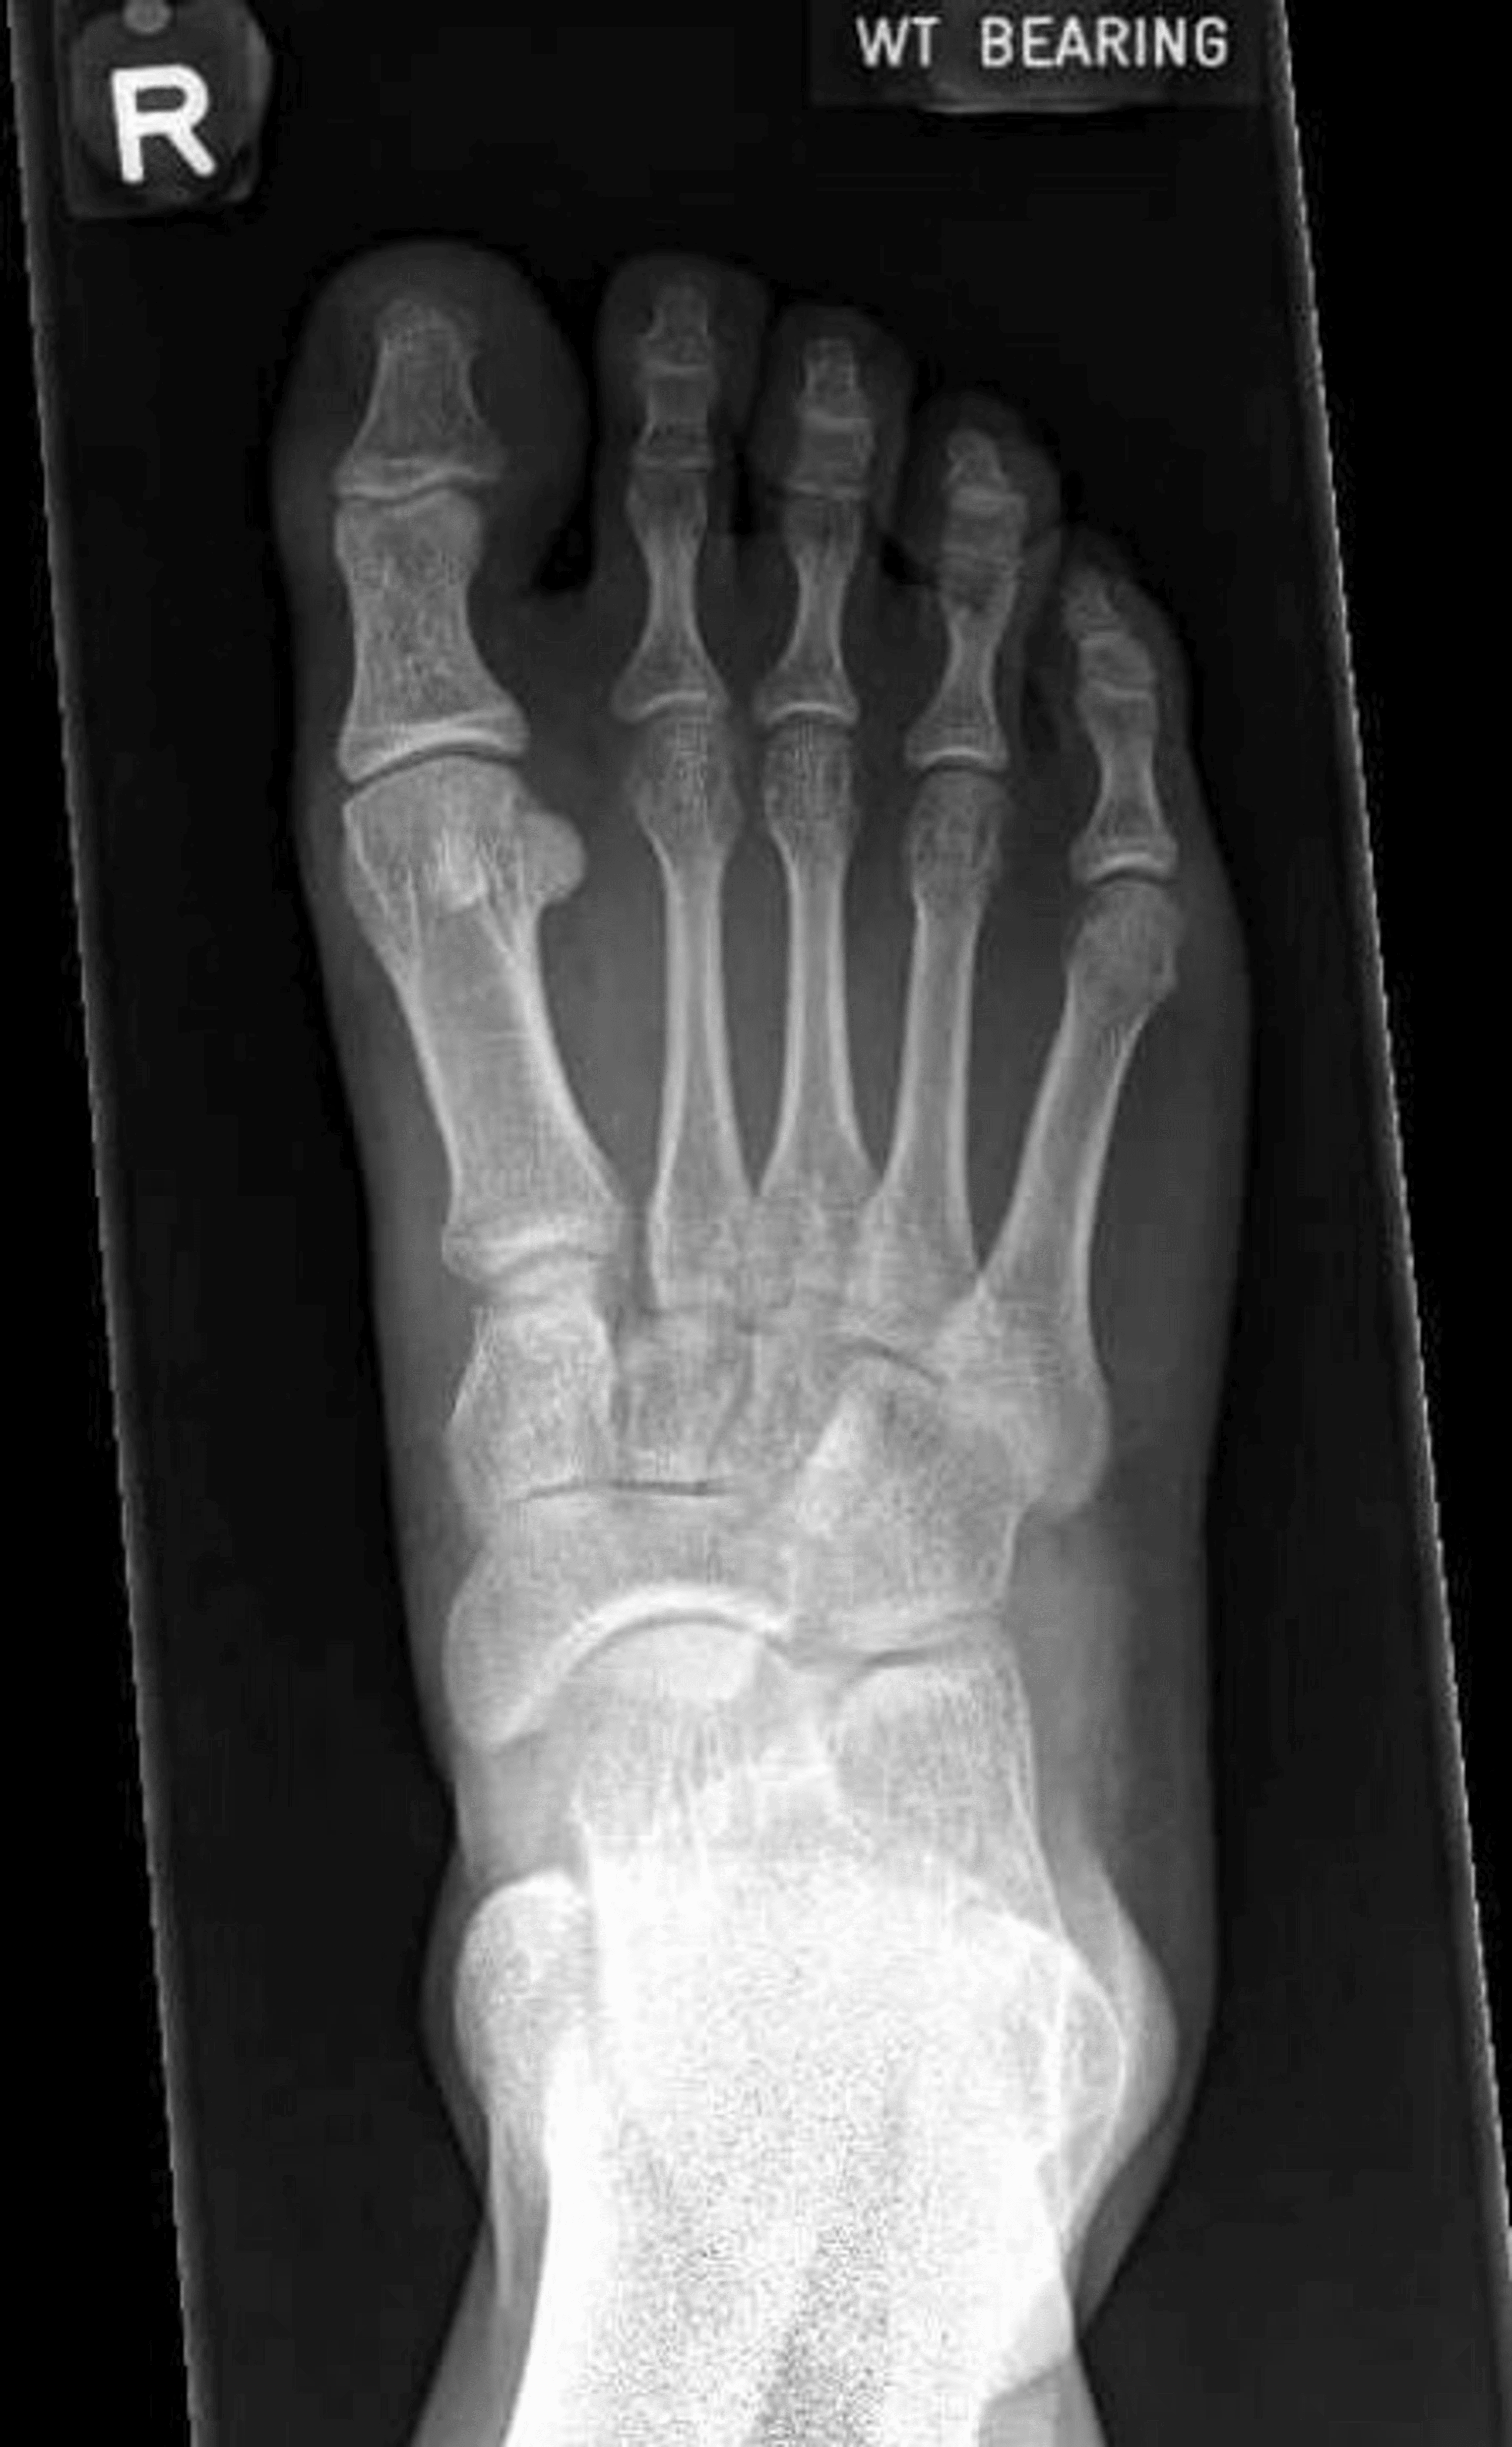

Diagnosing a Lisfranc Injury r/orthopaedics How Long Does It Take To Heal A Lisfranc Injury Some milder lisfranc injuries can heal on their own. With conservative treatment, even mild lisfranc injuries can take up to 8 weeks to heal. For those experiencing strains or sprains, recovery could take six to. The midfoot is the middle region of the foot, where a cluster of. They can take a long time to heal and may also require. How Long Does It Take To Heal A Lisfranc Injury.